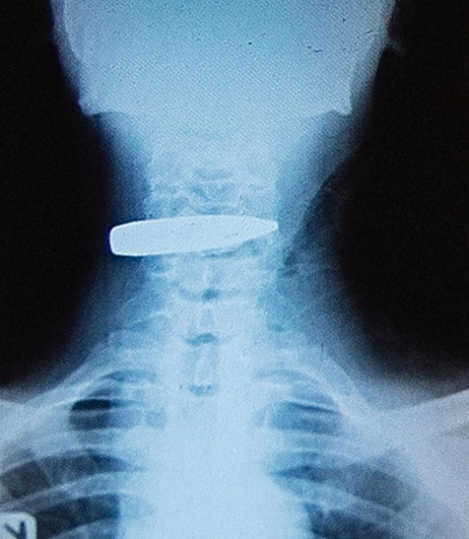

I had long conversations with soldiers about how they got wounded in battle.They told me how grateful they were to be alive, some of their colleagues weren’t as lucky. I also got to speak with medical personnel, on the uniqueness of their work in a war against terror. I’ll share all their stories here and start by introducing Soldier X, who I never met, but made a photograph of his Xray .An anti aircraft bullet, big and strong enough to tear through the titanium body of an airplane, was lodged in his throat, and for some reason, it didn’t blow his head off, this soldier lived through his surgery and got to take the removed bullet home as a reminder. This is a wicked wicked war!Why would anyone chose weapons made to attack war planes and use it on a fellow human … At close range ..Even in war there should be rules. Lieutenant Ologodo told me something really important, that if you don’t believe in God, working here will make a convert out of you, the frequency of witnessing the darkest of evil deeds, along side what can only be miraculous, will open your heart somehow.This is such a brutally wicked war !#tybellophotography #portrait